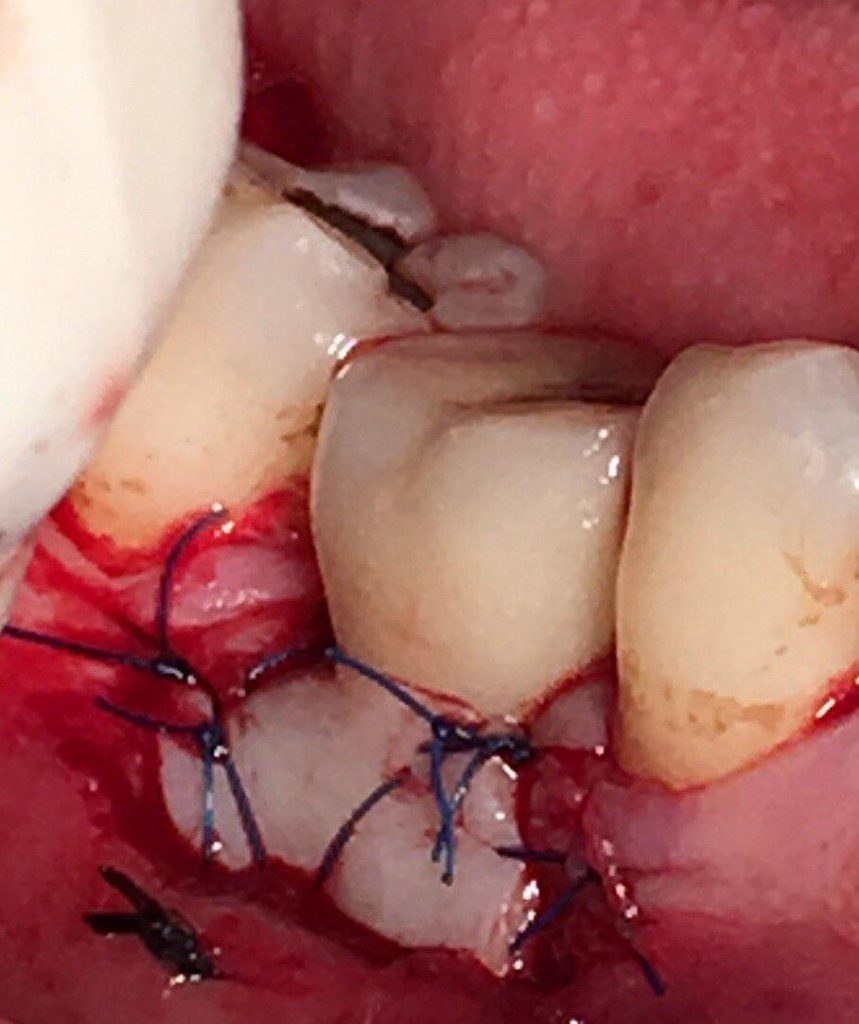

جراحی پیوند لثه جهت افزایش لثه چسبنده و پوشش ریشه و بهبود تحلیل لثه

جراحی افزايش طول تاج جهت آماده سازی دندانها برای ترمیم و گذاشتن روکش